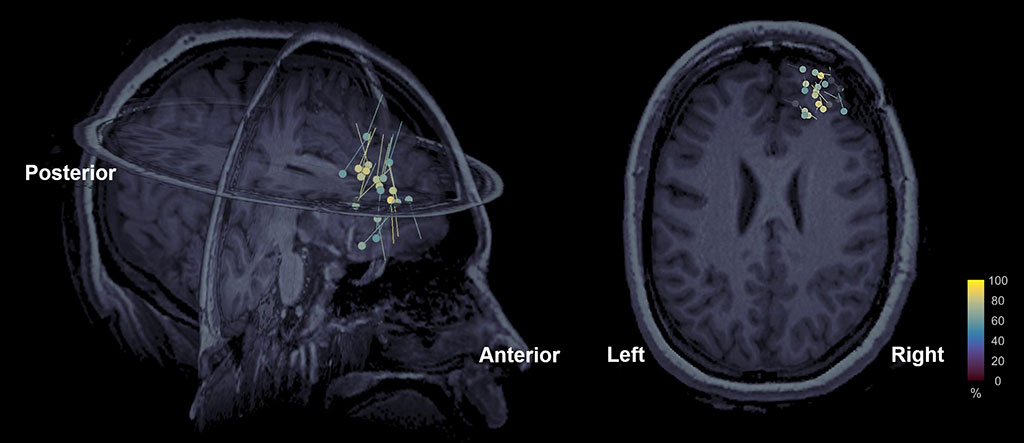

HD-EEG is usually combined with a magnetic resonance imaging (MRI) to get what is called electric source imaging (ESI), which offers precise localization (spatial location) of brain activity (as dipoles) millisecond by millisecond. ESI is often used in clinical practice for the precise localization of epileptogenic tissue in patients with epilepsy who are unable to control their seizures with seizure medications (Fig. 2). Derivatives of the HD-EEG technique include evoked potentials, which involves averaging the EEG activity time-locked to the presentation of a stimulus of some sort (visual, somatosensory, or auditory) or a child’s response (motor). Event-related potentials (ERPs) refer to averaged EEG responses that are time-locked to more complex processing of stimuli. This technique is used for the localization of eloquent areas in the human brain during presurgical mapping as well as to help us better understand the function of the human brain and to monitor functional brain plasticity in response to rehabilitation.